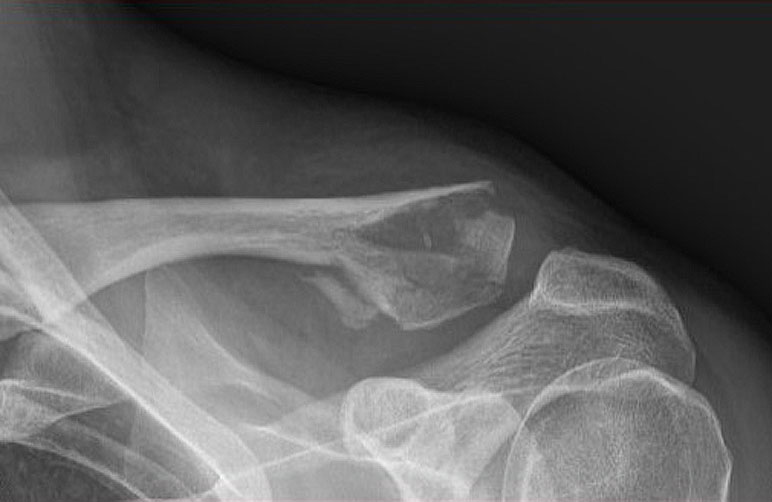

What do clavicle fractures look like on X-ray?

Below are examples of typical fractures that benefit from surgery.

Click an image to enlarge